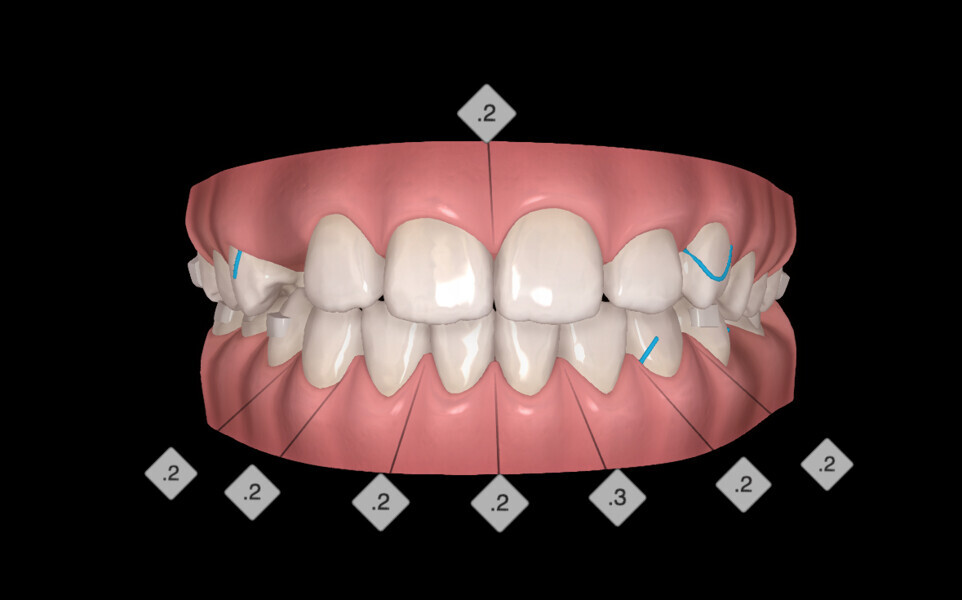

The digital treatment plan (ClinCheck) provided 18 aligners in each arch. The treatment objectives were focused on aligning and levelling the mandibular arch without excessively proclining the mandibular incisors, in order to control the Class III skeletal malocclusion by means of interproximal reduction and slicing of tooth #85. In the maxillary arch, the treatment plan focused on space creation for tooth #13 by distal rotation of the maxillary right molar and mesialisation of the maxillary right lateral incisor simultaneously to centre the midlines. Class II elastics were planned to control distal movement on the right side, and triangular elastics on the high canine were planned on the left side with button cutouts for the aligners. Lateral and posterior maxillary torque were planned to be close to 0° to achieve wider arch design and ideal intercuspation. No digital over-engineering was planned in the set-up, and lingual attachments according to personal preference were placed in the maxillary arch for aesthetic and biomechanical reasons (Figs. 15–19). Eruption compensation for tooth #13 was employed. Because of the age of the patient, the aligners were changed every seven days over the treatment period of less than five months.

At the end of the first stage of aligner treatment (Figs. 20–24), the auxiliary phase began with the bonding of two MTAs on the maxillary right premolars. A 0.016-in Australian archwire, shaped into a cantilever configuration, was then inserted into the MTAs, and a cutout was created on the final aligner. To prevent rotation, the archwire was cinched distal to tooth #15 and the cinch covered with composite.